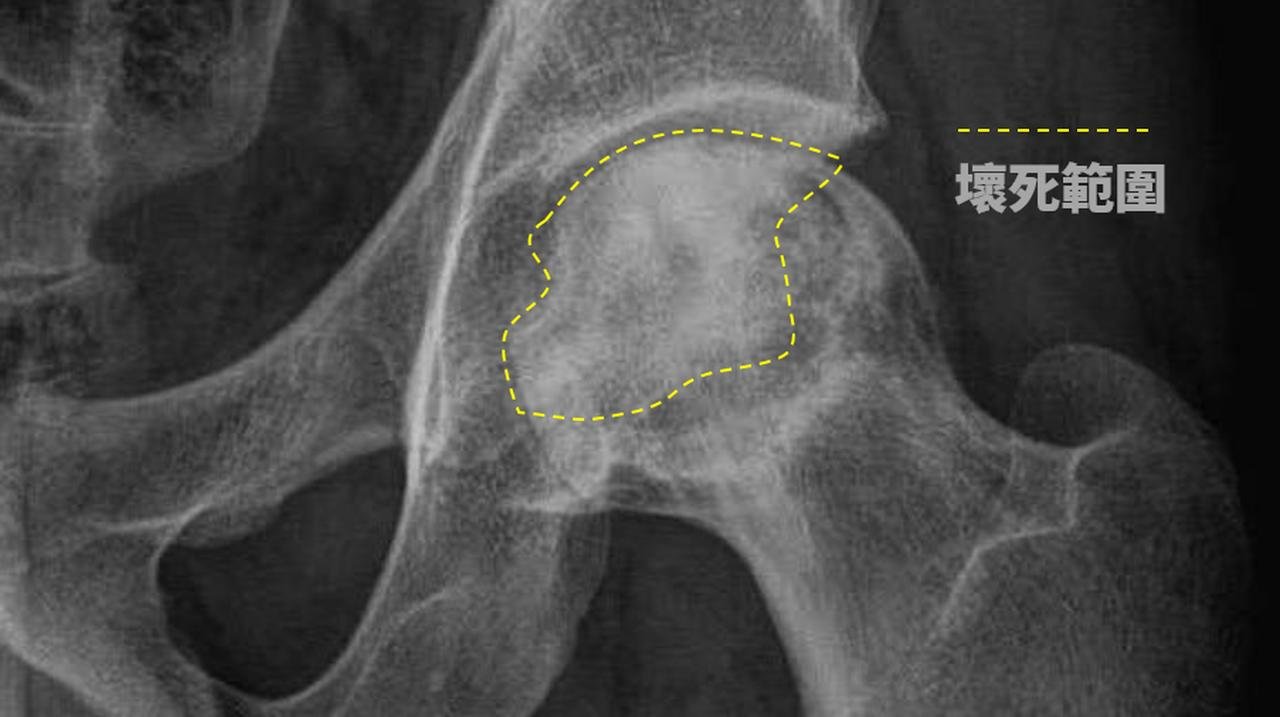

股骨頭缺血性壞死-x光(局部)。(朴子醫院提供)

賴彥州醫師分享兩個案例,分別是50歲與52歲的男性病患,因長期飲酒在行走時感到髖部疼痛,甚至呈現跛行現象,最終診斷出「股骨頭缺血性壞死」。

賴彥州醫師說,一般股骨頭缺血性壞死,通常是因外力造成,例如車禍或摔倒,導致股骨頭移位性骨折或脫臼,進而斷裂血管,引發缺血性壞死,但這兩位病患卻是由於長期飲酒所導致。研究指出,飲酒者罹患股骨頭缺血性壞死的風險是不飲酒者的3到13倍,風險隨著酒精攝入量和飲酒時間增加而上升。

賴醫師說贏,酗酒對骨骼的影響,主要體現在骨細胞血液中的栓塞,影響脂肪代謝,進而引發股骨頭缺血性壞死。兩位患者的情況顯示,股骨頭已出現半月狀,即軟骨下方的骨頭已經壞死,且關節面已崩塌,為改善患者生活品質,建議進行半人工髖關節置換手術,手術後,兩位患者康復良好,不再感到疼痛,能夠自如地行動。然而,醫師提醒患者在康復期間需謹慎,避免過度彎腰、蹲下、提重物或跑跳,以確保手術效果最大化。